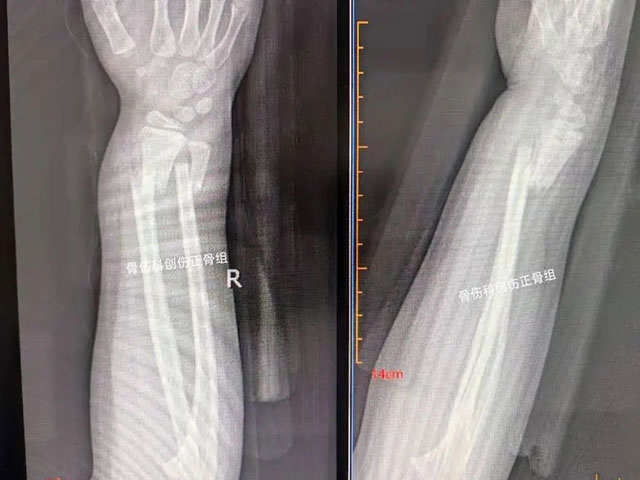

6岁的宇宇在学校玩耍时不慎摔伤右手,家属带其前往就近医院就诊,诊断为尺桡骨双骨折,建议其手术治疗。家属多方打听得知西南医科大学附属中医医院骨伤科创伤·正骨组开展的中医正骨手法复位可以不用手术,便前来就诊。

术前影像

术后复查

王念武主治中医师通过仔细阅片

分析受伤机理后

采用中医正骨八法中

拔伸牵引、升降提按

折叠环绕等手法

为宇宇进行骨折手法整复

仅仅1分钟就完成了骨折复位,宇宇的疼痛明显减轻了,手部畸形也消失了。骨折复位后再外敷上本院中医特色院内制剂,用特制的杉树皮小夹板包扎固定。6周后,骨折愈合,宇宇手部活动自如。